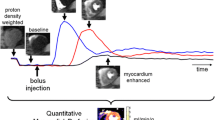

In-vivo quantification of cardiac perfusion is of great research and clinical value. The dual-bolus strategy is universally used in clinical protocols but has known limitations. The dual-saturation acquisition strategy has been proposed as a more accurate alternative, but has not been validated across the wide range of perfusion rates encountered clinically. Dual-saturation acquisition also lacks a clinically-applicable procedure for optimizing parameter selection. Here we present a comprehensive validation study of dual-saturation strategy in vitro and in vivo.

An alternative approach is dual-saturation acquisition, in which AIF and myocardial tissue information are collected after injection of a single bolus of undiluted contrast agent [13]. In this approach, signal saturation during AIF definition is avoided by using a short saturation time, and myocardial tissue information is subsequently obtained with longer saturation times [13,14]. MBF estimation by this method requires careful control of three parameters: saturation times for accurate evaluation of contrast enhancement in the blood pool and cardiac muscle; R2* effects, especially during AIF estimation [15]; and the influence of k-space ordering during high resolution image read-out [16].

The purpose of this study was to define a clinically useful procedure for accurate quantification of myocardial perfusion using the dual-saturation strategy. Using state-of-the-art 3Tesla-CMR, we analyzed the influence of saturation time (TS), echo time (TE), contrast injection rate, and image profile ordering on estimates of AIF and myocardial contrast uptake in a set of in-vitro (phantom) and in-vivo (large animal model) experiments (Figure 1). Signal acquisition and modeling derived from the in vitro analysis were incorporated in an in vivo comparison of the dual-bolus and dual-saturation strategies over a wide range of perfusion values, including hypo-perfusion (post-infarct), normal, and hyperemic MBF (pharmacological hyperemia), revealing generation of accurate MBF maps by dual-saturation CMR.